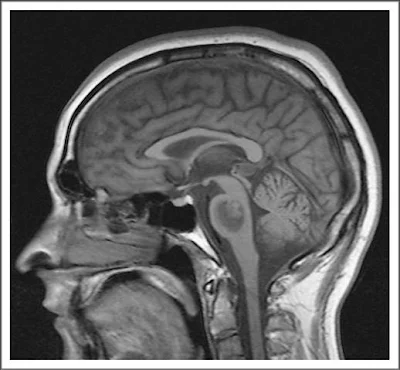

Cual es el diagnóstico? Mielinolisis central pontina.

La RMN revela mielinolisis central pontina, con una lesión

bien definida en la protuberancia de baja intensidad de señal en T-1, con indemnidad de los tractos ventro lateral y cortical; no hay efecto de masa ocupante de espacio ni distorsión del cuarto ventrículo adyacente. La mielinolisis central pontina es una condición desmielinizante no inflamatoria, de la sustancia blanca central, originalmente descripta en pacientes con alcoholismo crónico. Actualmente se ve más en cuadros asociados a corrección rápida de estados de hiponatremia con soluciones hiperosmolares